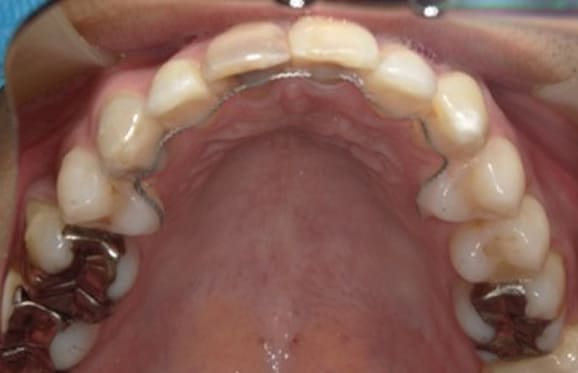

クリアブラケットを選択された患者様はホワイトワイヤーと透明ゴムを使用することで、見た目が目立ちにくくなります。また、各色カラーゴムもご用意しており、追加料金はかからずに選んでいただけます。

藤沢デンタルオフィスのワイヤー矯正 藤沢デンタルオフィスのワイヤー矯正